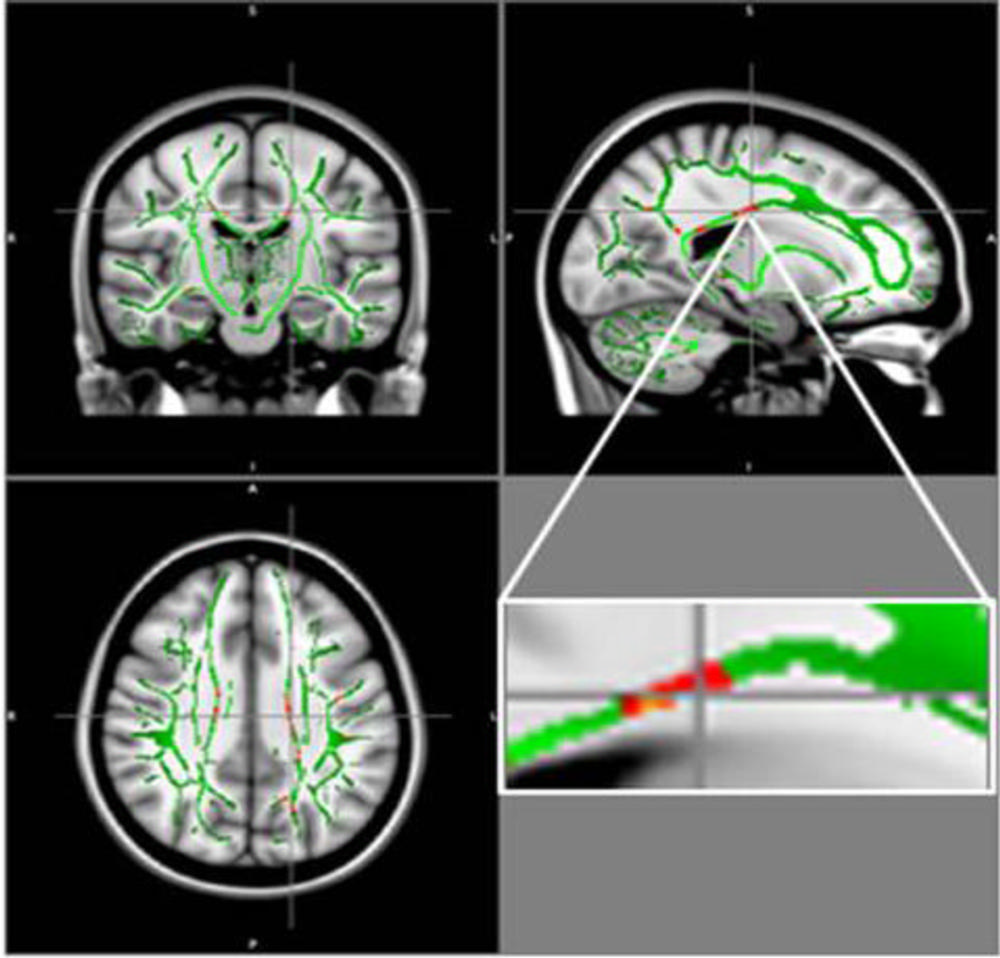

For the new study, researchers compared DTI results in 59 obese adolescents and 61 healthy adolescents, ages 12 to 16 years. From DTI, the researchers derived a measure called fractional anisotropy (FA), which correlates with the condition of the brain's white matter. A reduction in FA is indicative of increasing damage in the white matter.

The results showed a reduction of FA values in the obese adolescents in regions located in the corpus callosum, a bundle of nerve fibers that connects the left and right hemispheres of the brain. Decrease of FA was also found in the middle orbitofrontal gyrus, a brain region related to emotional control and the reward circuit. None of the brain regions in obese patients had increased FA.

Figure 1. Reduction in fractional anisotropy (FA) in obese patients compared to the control group: At the intersection of the alignment vectors, a large cluster of FA decrease located in the corpus callosum on the left. In red: Reduction of FA in obese patients compared to controls, and FA skeleton (green), superimposed on the mean of FA images in sample.